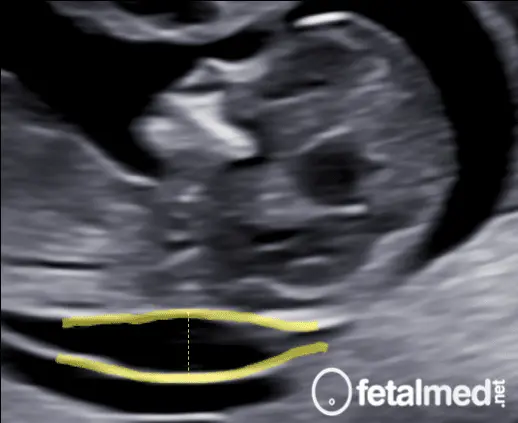

No exame de ultrassom, a TN aparece como uma faixa escura (translúcida) entre duas linhas brancas — uma correspondente à pele do feto e outra ao tecido subcutâneo. A espessura desse espaço, medida em milímetros, é o que chamamos de medida da translucência nucal.

Medida da translucência nucal no ultrassom de primeiro trimestre — faixa translúcida na nuca do feto

A translucência nucal é a área translúcida atrás da nuca do feto, visível ao ultrassom.